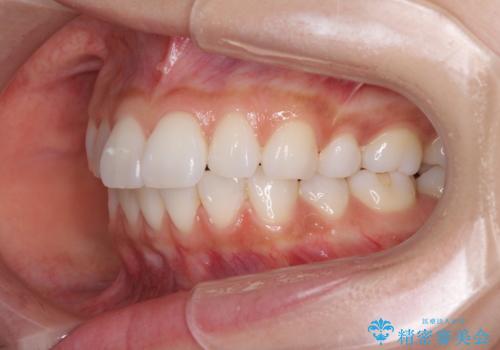

矯正治療の後戻り インビザラインによる再矯正治療

- 以前ワイヤー装置にて行った抜歯矯正の後戻りを気にして来院された患者様です。

前歯のデコボコにより、やや口元が突出した印象となっていたため、口元も引っ込めることとしました。

上下顎前歯に積極的にIPR(歯と歯の間を削る)を行い、インビザラインを用いて治療していくこととしました。

デコボコが解消されるのはもちろんのこと、突出感のあった前歯を引っ込めることができ、患者様には大変満足していただきました。